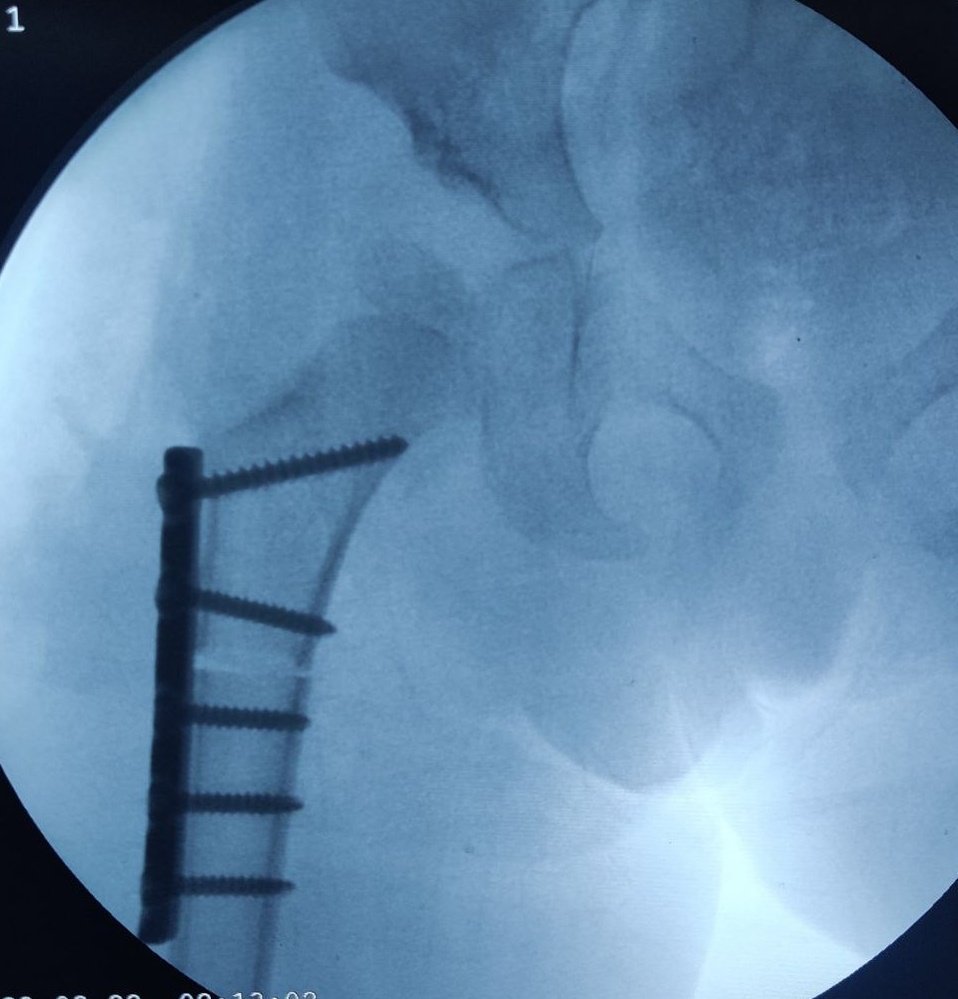

Illustrating below a case whether the Derotation osteotomy was done first and the we decided the acetabular osteotomy based on the cartilage cover on arthrogram.

The state of hip before the osteotomy. Open reduction was done elsewhere about a year ago. Persistent hip dysplasia was observed.

The Derotation osteotomy improved the coverage but we still have to decide about the acetabular procedure.

An arthrogram reveals a large cartilage cover on superolateral acetabulum. The cartilage bump is pointed to by the forceps.

The C Arm image is superimposed and an artist’s impression is drawn showing what the cartilage would look like in 3D. This offers an excellent teaching tool and a 3D orientation for young surgeons and pediatric orthopedic trainees to decide whether an acetabular osteotomy is needed

The surgeon would then discuss with parents and opt to continue an acetabular procedure of take a staged approach